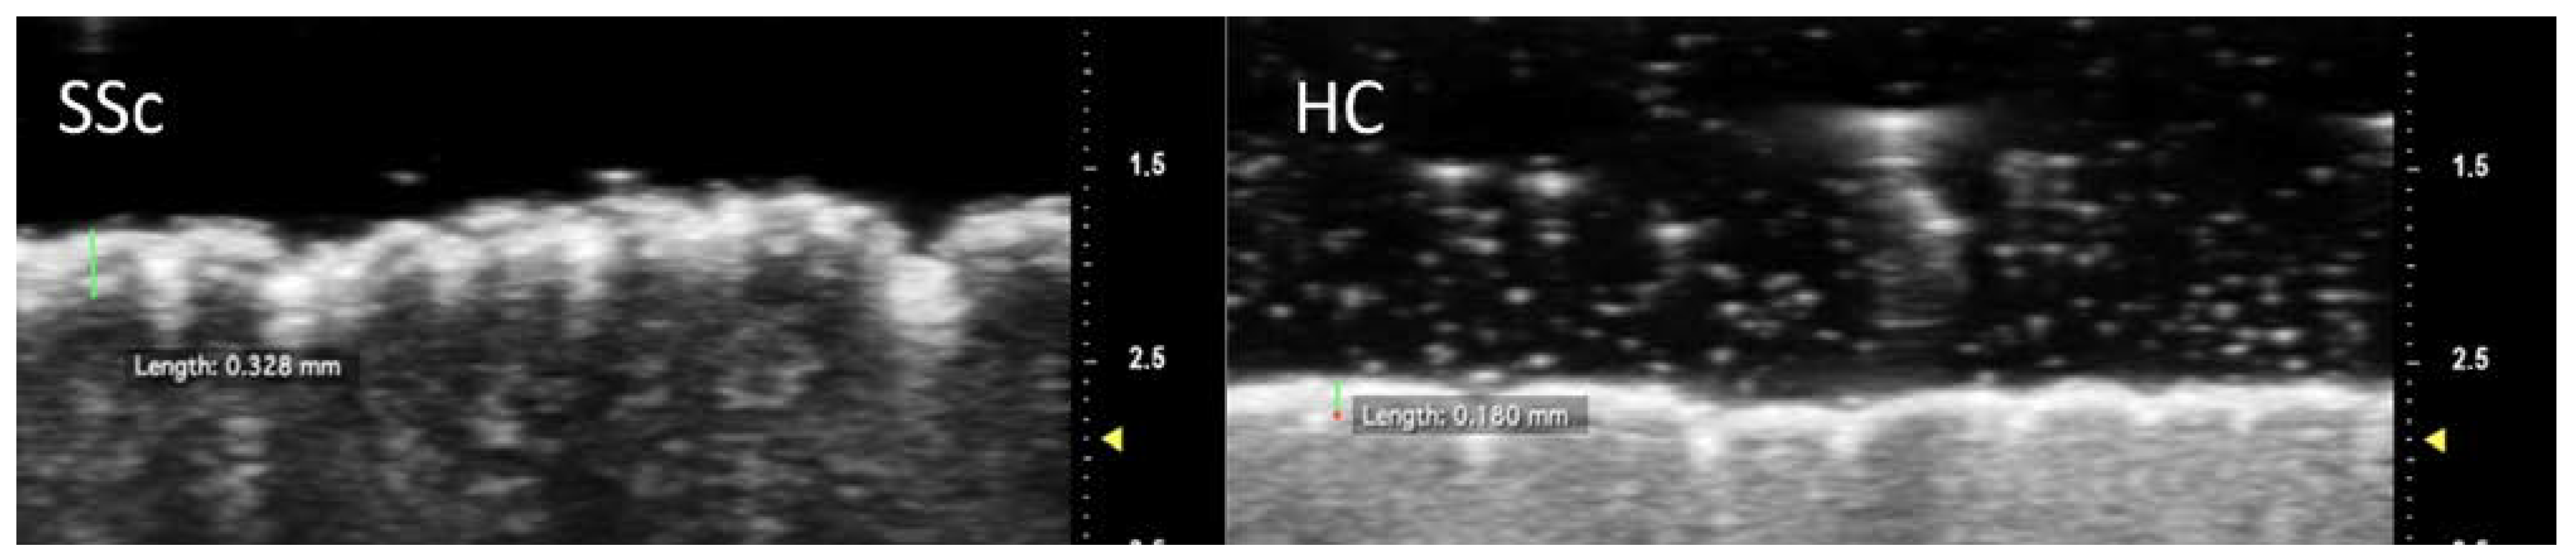

Table 2 summarizes the main UHFUS findings in our cohort. When performing UHFUS between SSc patients and HC, the former had a significantly thicker epidermal layer in all the different regions of interest (p < 0.001 for all)—Figure 2.

Figure 2.

Measurement of epidermal thickness at the intermediate phalanx of the second finger. Note the increased thickness of the epidermal layer in the SSc patient compared to the control subject.

The SSc group also presented lower epidermal MGV at DP, IP and PP (p = 0.01 for all). Similarly, low values of dermal MGV reached statistical significance at DP (p < 0.001), IP (p = 0.006) and PP (p = 0.04)—Figure 3. When UHFUS results were diversified according to skin subset, both lcSSc and dcSSc reconfirmed a significantly thicker epidermal layer than HC for all the regions of interest. Noteworthy, when considering MGV differences between cutaneous subsets and HC, statistically significant lower values were detected for both skin subsets only at the dermal layer of DP (p = 0.001 for lcSSc; p = 0.008 for dcSSc) and IP (p = 0.05 for lcSSc; p = 0.01 for dcSSc).